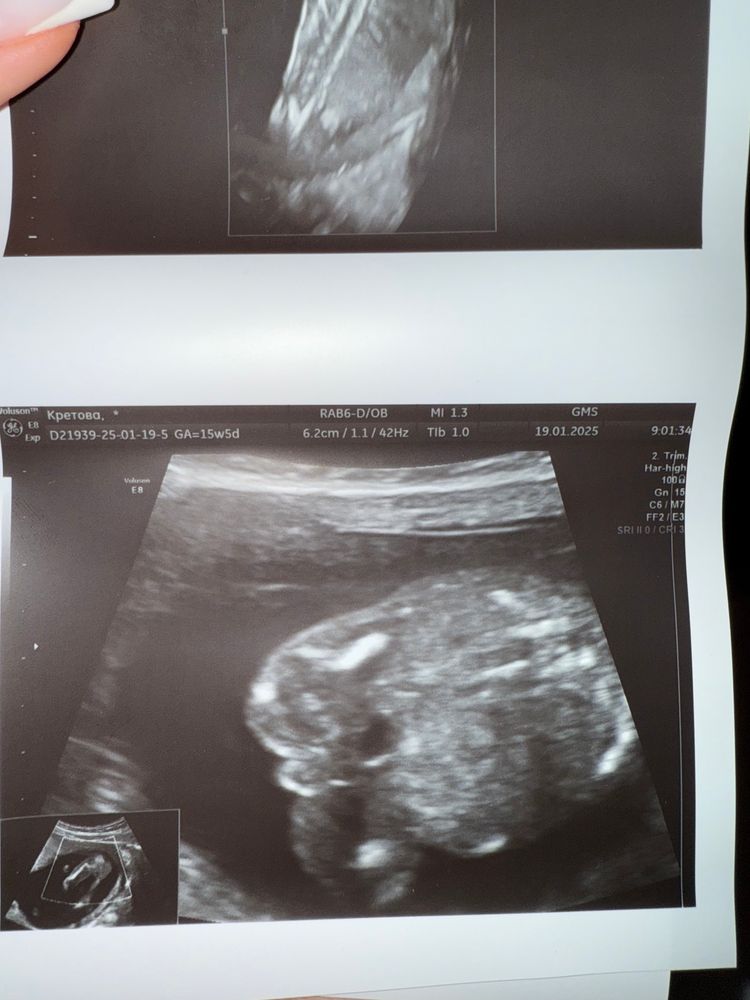

С первого скринга жаркие споры по поводу пола нашего малыша 😁 Сегодня 15 недель 5 дней, но по размеру плода мне ставят 15 и 2. На ранних сроках чуть позже увидели эмбрион (я еще испугалась, что его нет в пя), в итоге сказали, что вероятнее всего, была поздняя овуляция.

сегодгя было сложно что-то рассмотреть, с нетерпением жду 2 скрининга, но мне очень уж интересно, какого пола наше сокровище. Посмотрите на фотку и сделайте свои предположения, пожалуйста ☺️ Как я понимаю, это вид спереди😁

Юлия Флинк, в 15+4, искала высоко квалифицированного узиста и нашла, на приёме он мне объяснил, что на этом сроке мошонка уже ярко-выражена и отчётливо заметно, а у девчушек там более плавный бугорочек и почти не заметен. У вас я вижу что малыш сидит на попе и чётко заметно гениталии)